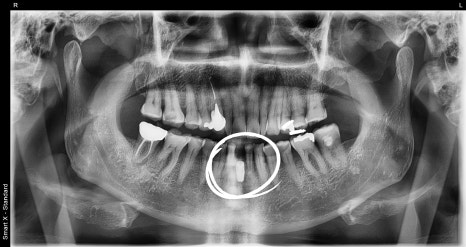

수술 직 후 엑스레이 사진

흔들리는 해당 치아를 발치하고,

같은 날 임플란트 식립과 골이식을 동시에 진행했습니다.

잇몸 뼈가 부족한 부위에는 골이식을 통해 안정적인 식립을 유도하였고,

심미성 회복을 위해 임시치아 제작도 함께 진행했습니다.